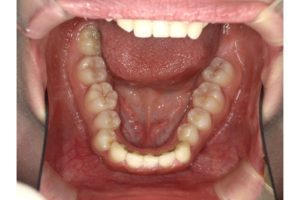

さて、皆さんは【歯の後戻り】についてご存知でしょうか?

歯はとても賢くて、元あった場所に戻ろうとする力を持っています。

この歯が元いた場所へ戻ることを【後戻り】と言います。

簡単にいうと、綺麗に並べた歯がまたガタガタになってしまうよという事ですね😶